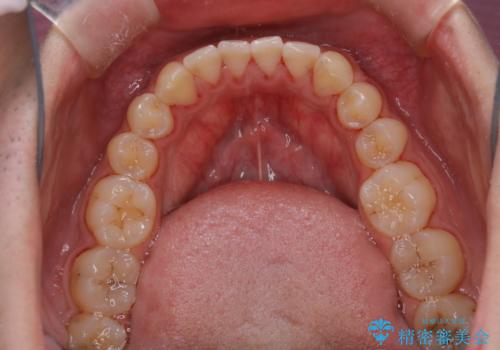

- 矯正治療を考えていて、歯科医院が久しぶりのためまずはクリーニングしたいとのことでした。PMTC60分コースを行いました。

今後、矯正を考えている場合は、まず現状の口腔内をチェックし、虫歯や歯周病などを早期に発見し進行を防ぐことが大切です。